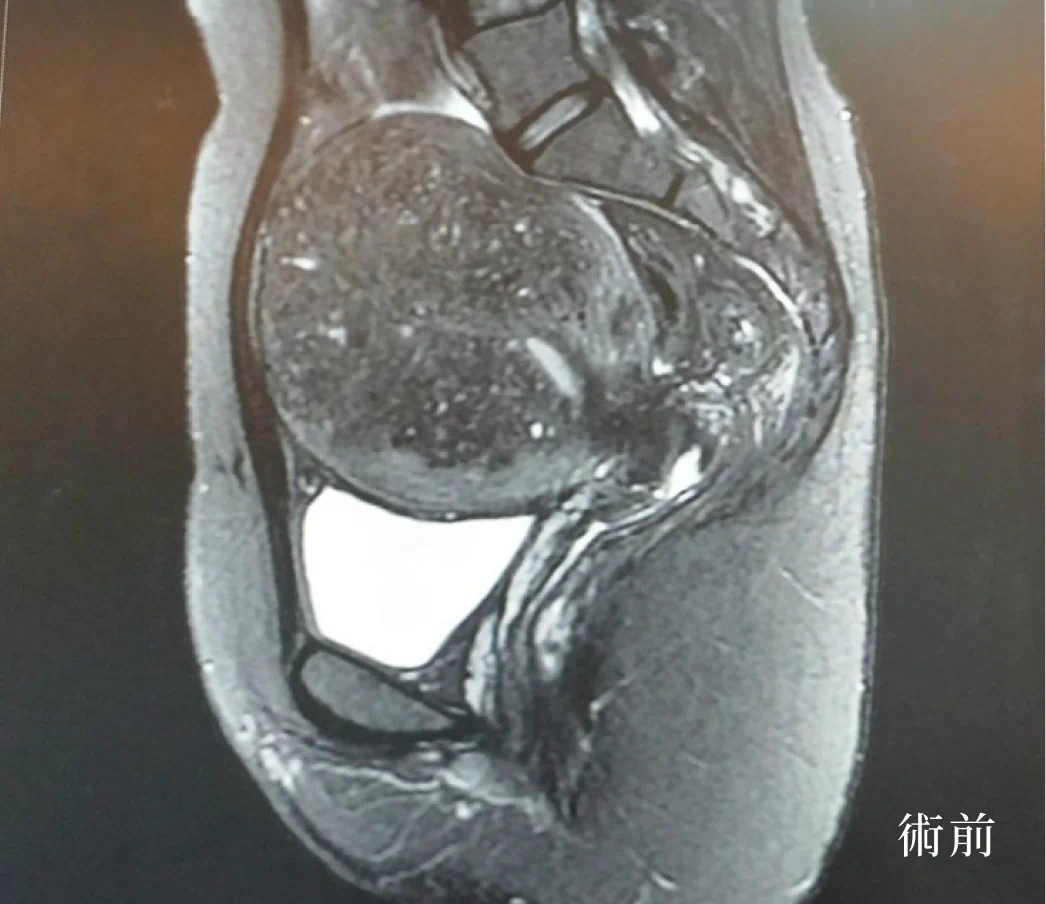

個案在海扶刀治療前,子宮肌瘤最大的約9*8 cm,經由吳昆哲醫師用海扶超音波聚焦消融術後,不僅表皮無傷口,做完手術的隔天即可出院,恢復正常的日常生活及輕鬆的返回職場工作。